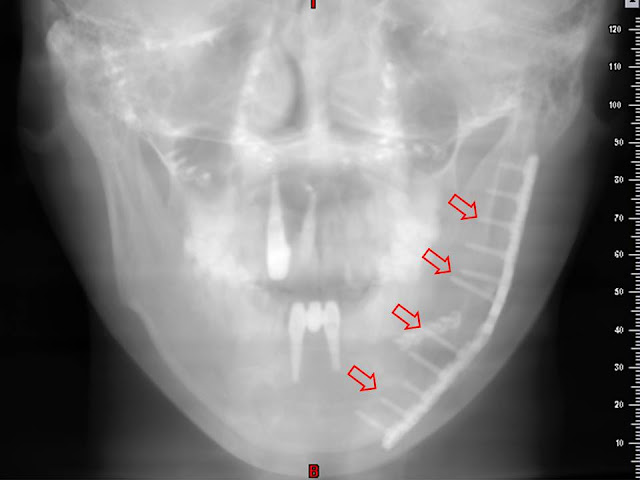

我們來看一些實際的案例。上圖左邊手術後一週的骨頭,

還可以明顯見到切開過的縫隙以及交界處的不平整,

但是右圖可見一年之後的骨骼癒合得相當理想,

所以絕大多數的情況下都不必擔心手術後的骨骼強度不足。

當然手術時若能盡量讓骨頭切開處緊密相接並牢牢固定,

對於骨頭的順利癒合絕對有極大幫助,連帶也有助於儘早張口復健以及咀嚼。 群英整形外科診所 發表在 痞客邦 留言(0) 人氣(1,097)